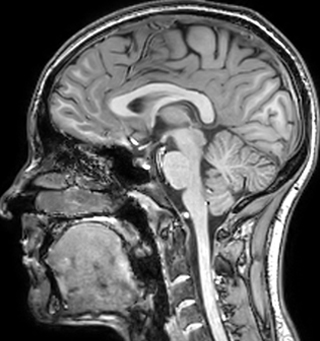

of limiting MWI to the brain, even without the cerebellum, we can now spend about the same amount of time and scan the whole brain and the cervical spinal cord, which is a huge boost for us.” Dr. Rauscher says, “For MWI we perform 3D T2 with 32 or more echoes. This used to take a long time, but with Compressed SENSE we can decrease this to ten minutes for the whole head. Because of the large field of view (FOV) on the readout direction, we even get information from the brainstem, which we previously missed when we were using the GRASE approach. Having the whole head scan is nice because it has spatial resolution, orientation and FOV that are comparable to the standard 3D clinical MS scans, including the FLAIR and 3D T2, and a 3D T1 for brain volume.”

T1 - Weighted, Myelin Water Fraction Superimposed

Spinal cord coverage

Smaller, more isotropic voxels

Excellent detail in quantitative maps

Images courtesy of Adam Dvorak, Department of Physics and Astronomy, University of British Columbia